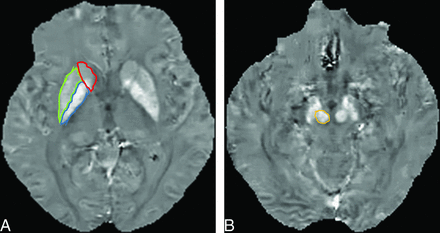

The susceptibility (S) of the deep gray matter structures was determined by using ImageJ software (National Institutes of Health, Bethesda, Maryland). For the major deep gray matter structures, excluding the SN, the mean S value of the bilateral globus pallidus (GP), red nucleus (RN), putamen (PT), and caudate nucleus (CN) were measured on axial QSM by 2 neuroradiologists (M.A. and Y.I., with 5 and 9 years of MR imaging experience, respectively). They were blinded to clinical and neurologic findings and independently placed ROIs on the structures (Fig 1). The unit of S measured on QSM was expressed as parts per billion.

A 59-year-old woman with Parkinson disease. A, QSM, axial section at the level of the basal ganglia. ROIs as large as possible were placed. Areas encircled in red, green, and blue are the caudate nucleus, putamen, and globus pallidus. B, QSM, axial section at the level of the midbrain. The encircled area identifies the red nucleus medial to the substantial nigra.